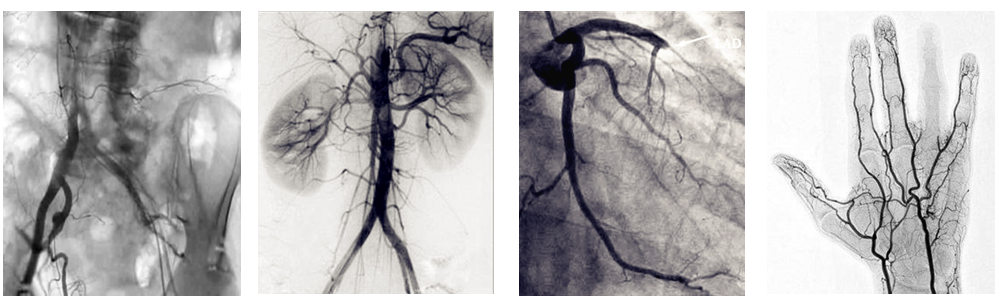

介入c臂機可以把不需要的組織影像刪除掉,只保留血管影像。圖像清晰,分辨率高,對觀察血管病變,血管狹窄的定位測量,診斷及介入治療提供了真實的立體圖像,還具有多種工作模式,靈活方便,滿足各種臨床需要,為各種介入治療提供了必備條件。

PLX7100A移動式介入c臂機,體積小,劑量低,圖像清晰,是廣大基層醫院介入腫瘤科以及三甲醫院??平槿?如肝膽外科、ERCP室、婦科)使用的理想設備。